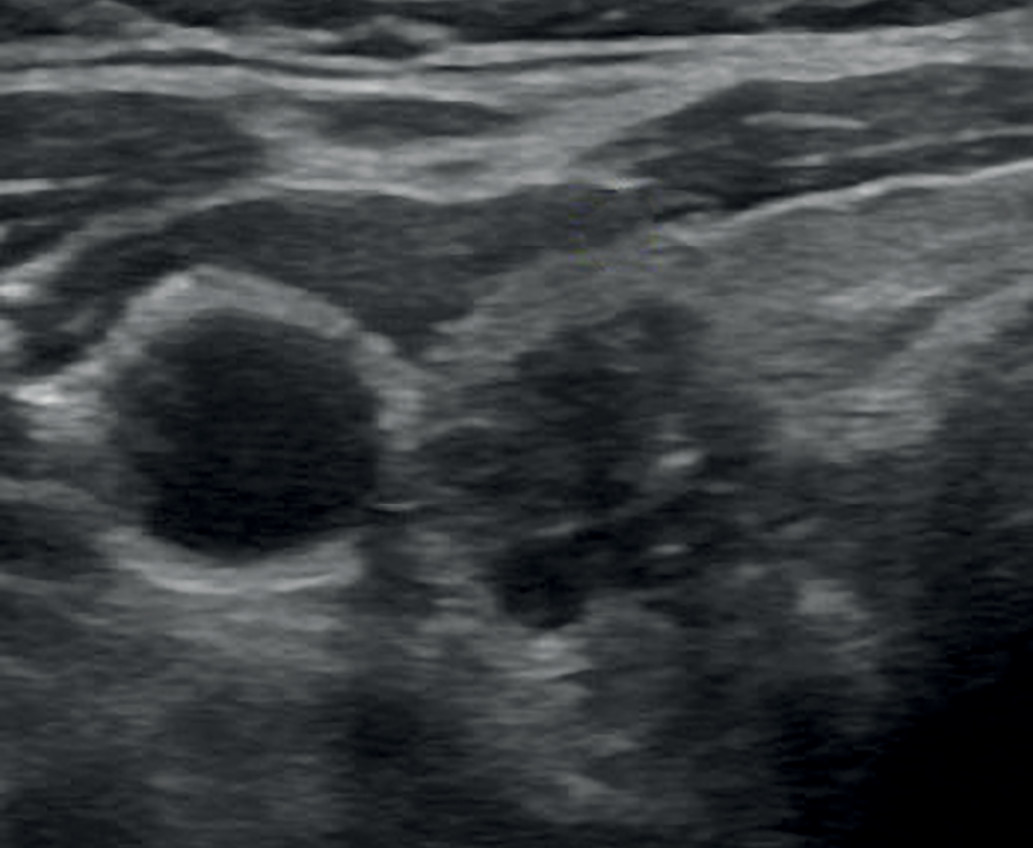

1. Рис. 1. Анэхогенное образование ЩЖ с перегородками (EU-TIRADS 2). | |